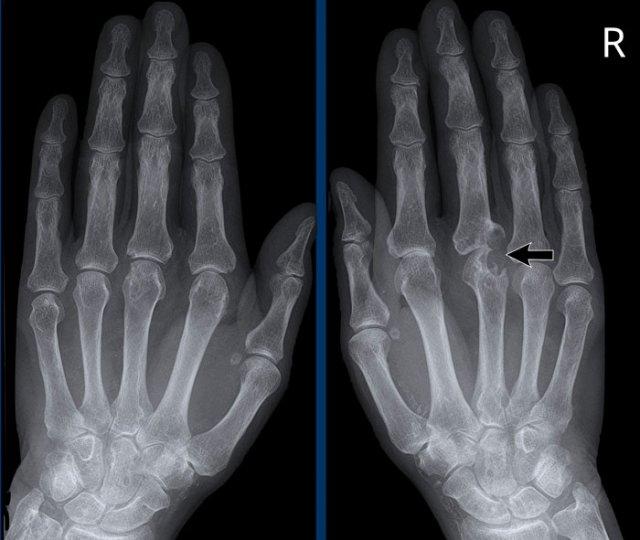

A

Hẹp khe khớp liên đốt xa (DIP) ngón 4 (mũi tên) kèm hình thành gai xương và xơ cứng xương dưới sụn.

B

Hẹp khe khớp liên đốt xa (DIP) ngón 2-5 không đối xứng kèm hình thành gai xương, xơ cứng xương dưới sụn và lệch trụ nhẹ của khớp DIP ngón 3 (mũi tên).

Các khớp liên đốt gần (PIP) cũng bị ảnh hưởng nhưng mức độ nhẹ hơn.